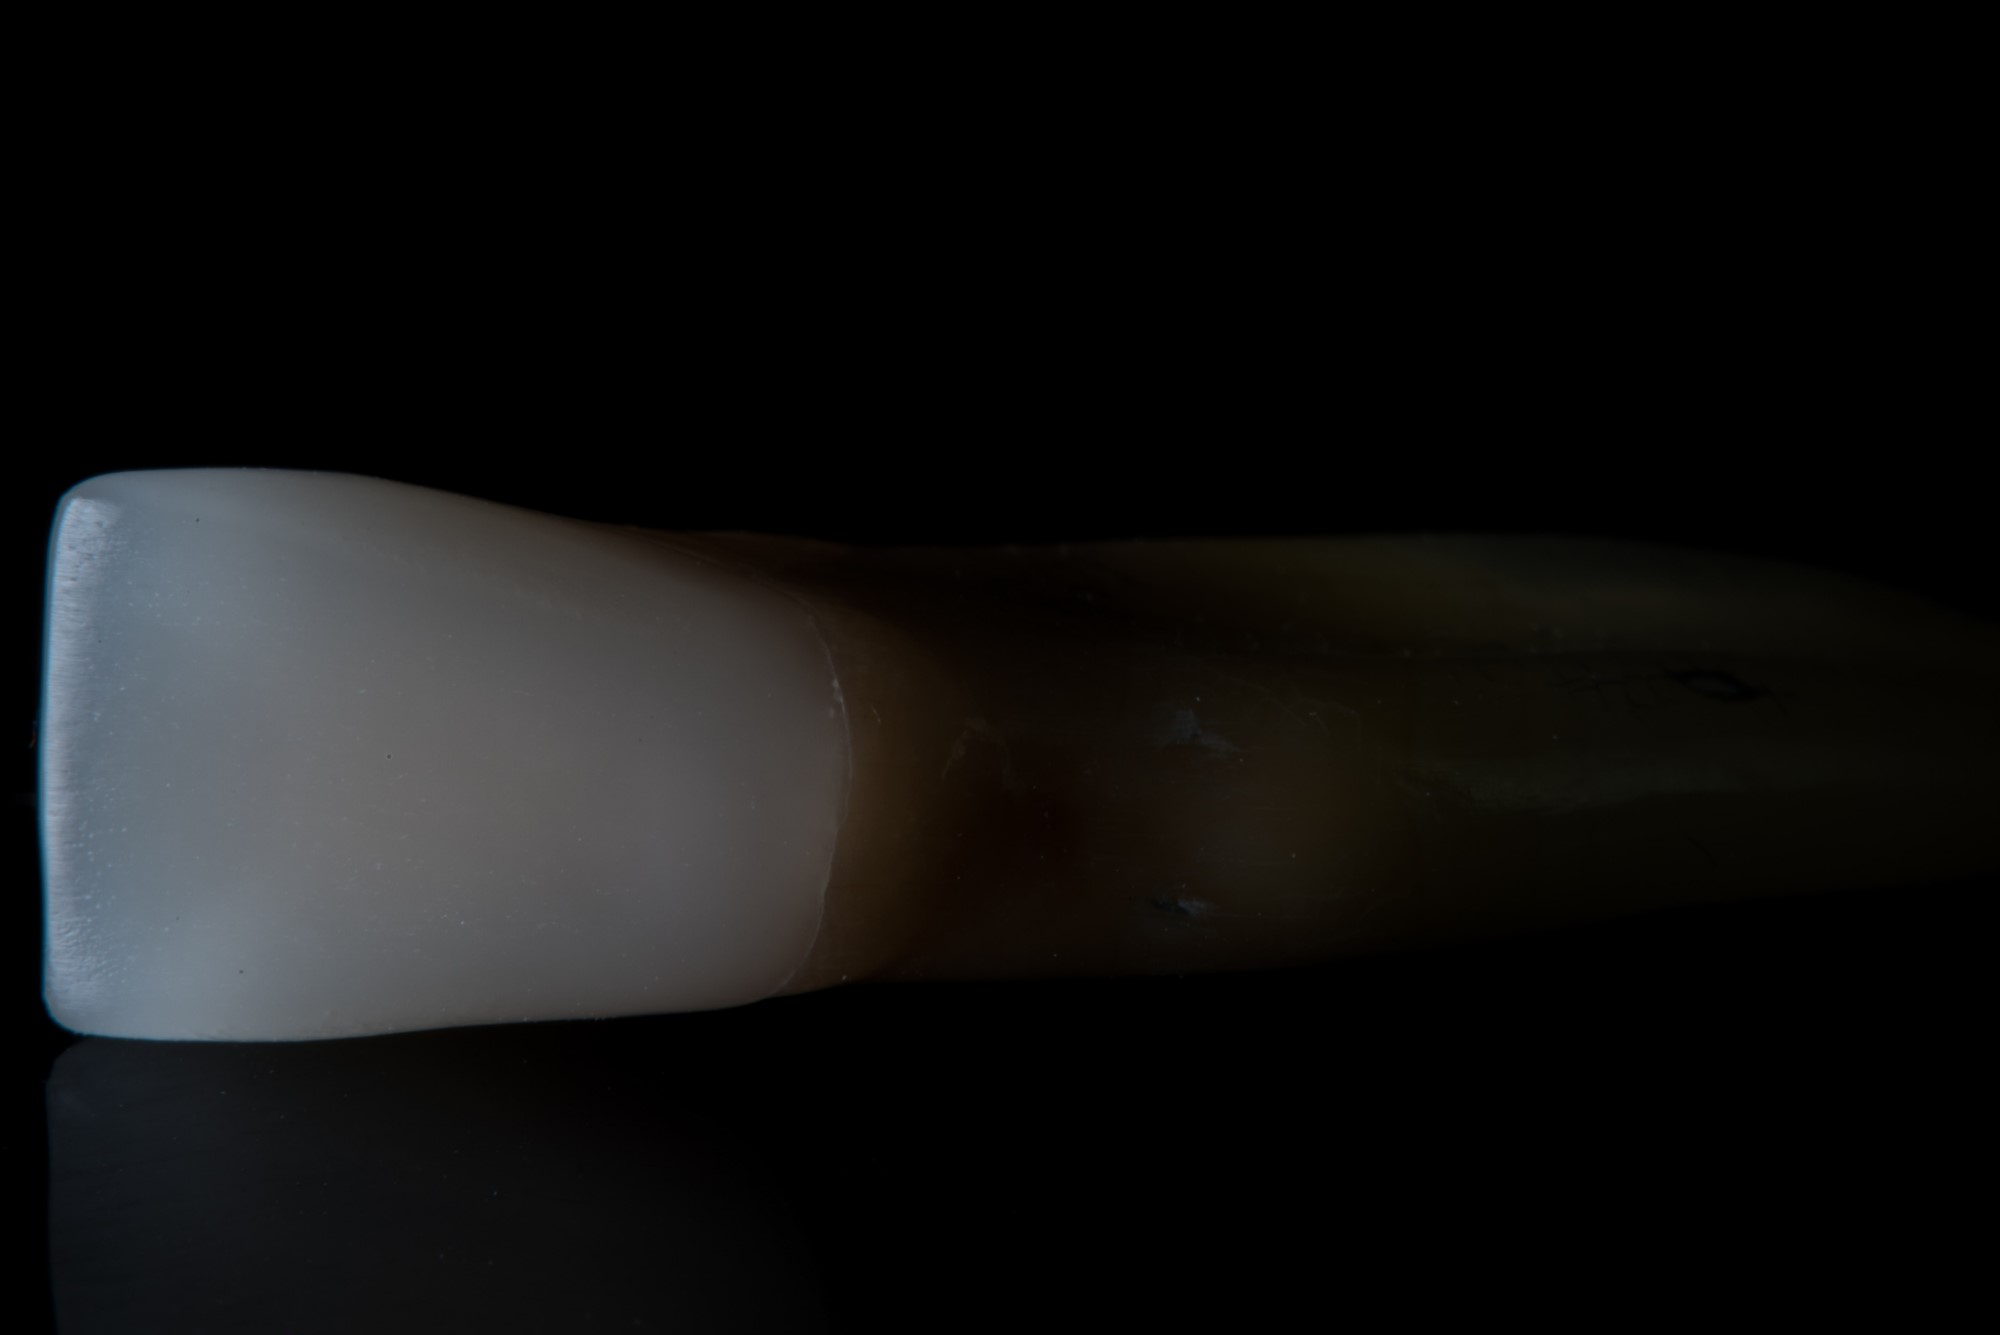

Fiksuoti dantų protezai apima įvairius sprendimus: galimas dantų protezavimas dantų karūnėlėmis, dantų užklotais arba tiltiniais dantų protezais. Be to, svarbu paminėti, jog priklausomai nuo atvejo, fiksuoti protezai gali būti dedami tiek ant dantų, tiek ir ant implantų. Abejais atvejais, protezais reikėtų rūpintis lyg savais dantimis.